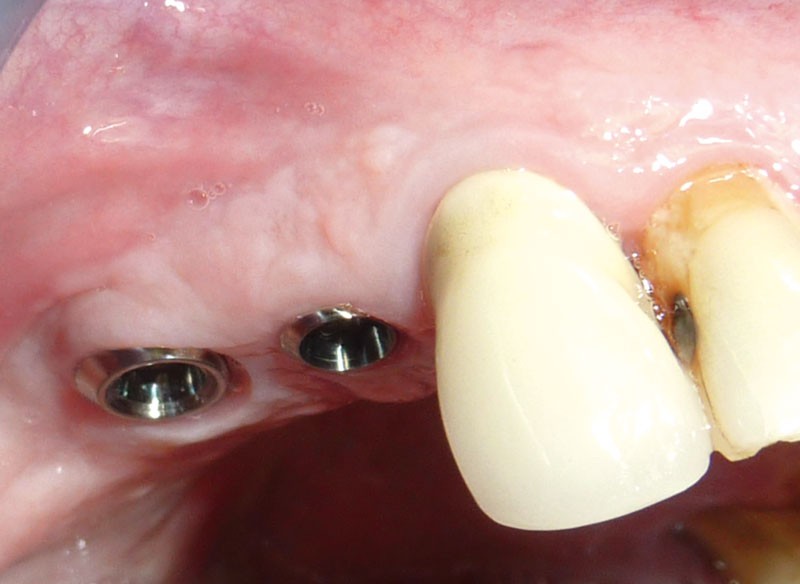

C’est cette dernière indication que nous allons illustrer avec trois cas cliniques. Le recours à l’implant à col long a simplifié la chirurgie et la prothèse, en évitant d’avoir recours à une technique de régénération osseuse guidée (ROG).

La perte osseuse vestibulaire dans ce secteur (fig. 3) ainsi…